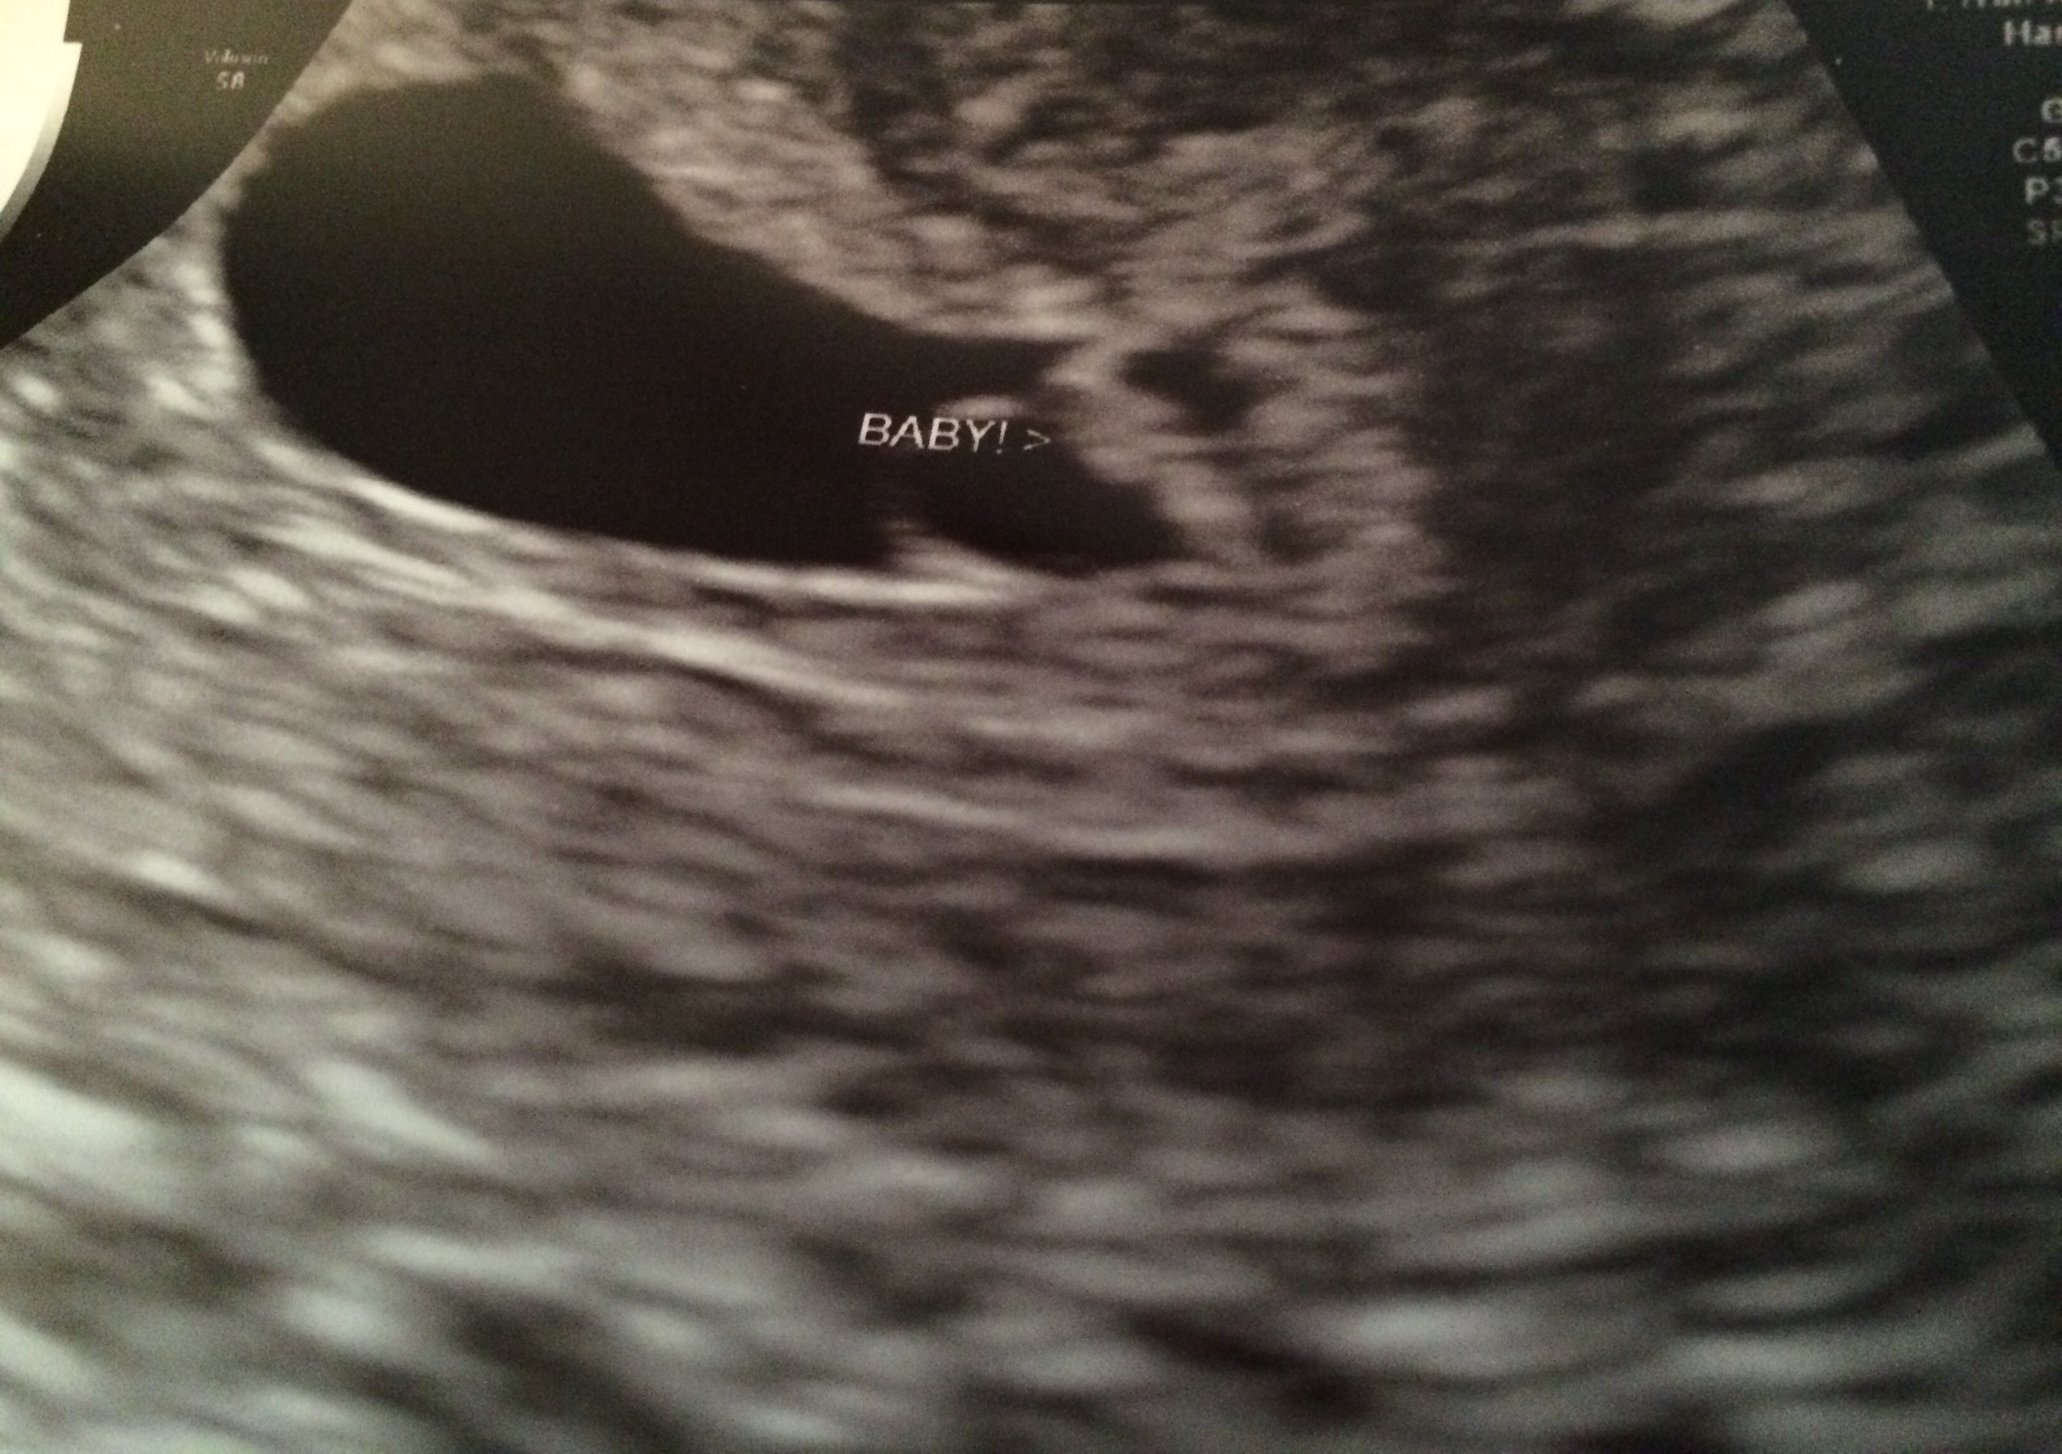

I feel so relieved! Doctor said everything looked great and we saw the heart beat